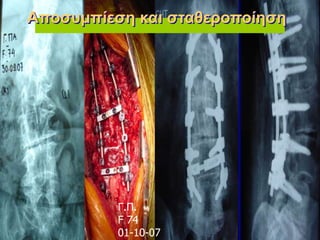

Γ.Π. F 74 01-10-07 Αποσυμπίεση και

σταθεροποίηση